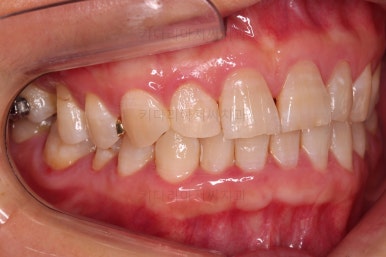

초진 때의 사진입니다.

전반적으로 치열이 삐뚤하고 불균일한 양상이긴 하지만 꼭 이런 부분들까지 교정을 해야 하는 건 아니에요.

치열에 대한 본인의 개선 의사가 있다면 전반적인 교정을 해줄 필요가 있지만 그렇지 않다면 굳이 할 필요가 없는거죠.